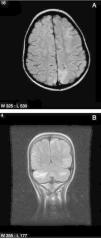

En 5 pacientes, las manifestaciones neurológicas cumplieron criterios de SEPR. En estos la sintomatología predominante consistió en: CE parciales (4 individuos), encefalopatía leve (4 individuos), cefalea (2 casos), temblor (2 casos) y alteraciones visuales (2 casos, uno visión borrosa y otro ceguera transitoria), desapareciendo progresivamente la sintomatología en las primeras 4 semanas de evolución. En un caso se detectó hipomagnesemia como factor predisponente. No se detectaron alteraciones significativas de la presión arterial ni de los niveles sanguíneos de tacrolimus en ningún paciente. En los estudios de RM craneal (fig. 1) se encontraron alteraciones de la intensidad de la señal de la sustancia blanca, mostrando en la secuencia FLAIR lesiones córtico-subcorticales fundamentalmente en lóbulos occipitales y parietales y, menos frecuentes, en lóbulos frontales y en cerebelo sugerentes, según el resultado del cálculo del coeficiente de difusión aparente en la difusión, de edema vasogénico. En el EEG, 3 pacientes presentaron actividad fundamental enlentecida para la edad y 2 pacientes actividad paroxística focal (punta-onda de localización parieto-occipital). Dos pacientes se trataron con levetiracetam de manera transitoria. Los controles posteriores de EEG fueron normales en todos los casos.

A) Resonancia magnética, imagen axial en secuencia FLAIR. Alteración de la intensidad de señal córtico-subcortical de localización occipital bilateral y frontal izquierda en territorio vascular frontera, características del SEPR. B) Resonancia magnética, imagen coronal en secuencia FLAIR. Múltiples hiperintensidades córtico-subcorticales en ambos hemisferios cerebelosos, y en áreas córtico-subcorticales parietal y temporal izquierdas compatibles con SEPR.